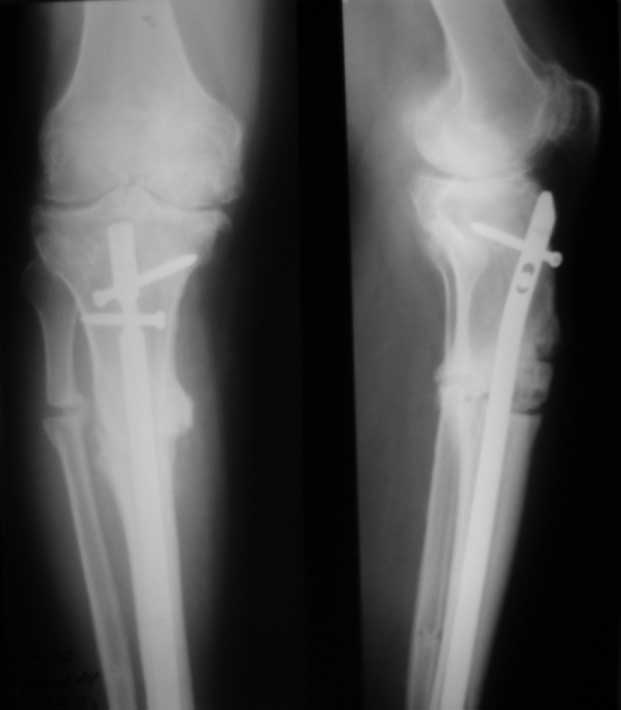

Пациент 8 мес после операции ТКА, в анамнезе неправильно сросшийся

перелом голени, коррекция оси (снимки прилагаются).

Глубокая инфекция исключена. Ротация бедренного компонента в норме (по

КТ).

насколько для такого ограничения критична некорректная установка б/б компонента (я

намерял 7 град)?